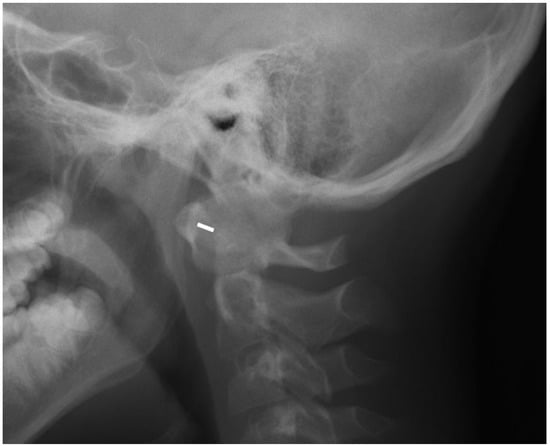

Several methods were used to measure vertical subluxation; the most frequently used methods were McGregor’s (cut off value: 4.5 mm) [13] or the Sakaguchi–Kauppi method. In the latter, vertical AAS is diagnosed when the superior facets of C2 crosses the line formed by the lower aspects of the anterior and posterior arches of C1 vertebra [14]. SAS was reported in patients with the displacement between the upper and lower endplates of adjacent vertebrae exceeding 2 mm (Figure 4) [15].

The cervical spine was affected in 35% (12 out of 34) of the included JIA patients (Table 2). SAS was the most common complication and was found in 8 out of 34 children with JIA (8/34, 24%) and in 2 subjects in non-JIA group (2/38, 5%, p = 0.039). All these cases were confirmed by radiography, while only two were seen in MRI. More cases diagnosed with radiography resulted from both the erect positioning of the patient and use of functional projections.

The most frequent abnormality was SAS. It was seen in eight out of all included patients with JIA (24%), all with 4.5 years history of JIA. All lesions were seen on radiographs, whereas only two were confirmed on MRI which results from the different position of a patient at each examination. In other studies, the prevalence of SAS was lower and affected 6–7% of JIA patients [6,8]. Most commonly, level C4/C5 was affected [8], which was also confirmed in the current study. The lower prevalence of SAS in the mentioned studies could resulted from the coexistence of apophyseal joint ankylosis, which hinders SAS. In this study, SAS was more frequently seen than in other studies with a similar low prevalence of ankylosis. However, this finding was interpreted with caution, bearing in mind that the SAS appearance may result from the natural flexibility of the pediatric cervical spine as seen in 5% of the current non-JIA group and was also described by other authors [17].

Figure 4. Lateral radiograph in flexion (indicated by white arrow) in a 13-year-old girl showing subaxial subluxation at C2/C3 level (black arrow).